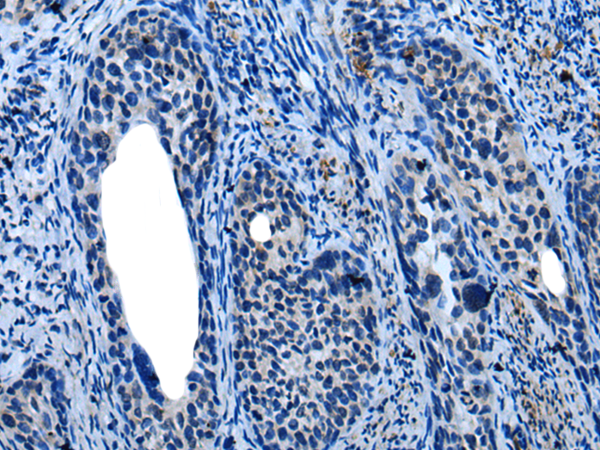

ELISA, IHC

IHC positive control:

Human tonsil and human cervical cancer

IHC Recommend dilution:

10-50